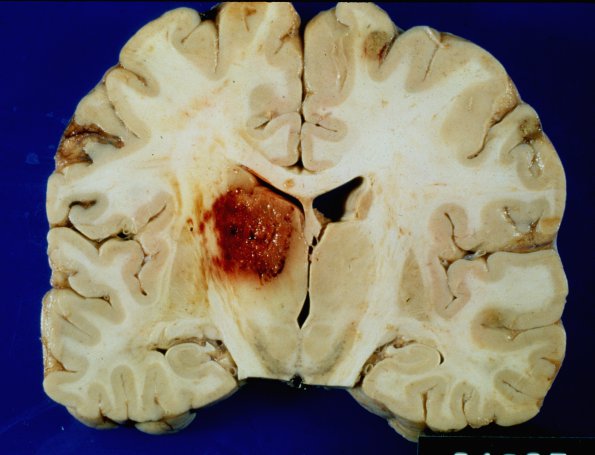

Washington University Experience | INFECTION | Fungus | Aspergillosis | 1 Aspergillosis - Gross Autopsy Neuropathology | 3A1 Aspergillosis (Case 3) infarct

3A-B A feathery hemorrhagic mass originating in the thalamus at several magnifications.